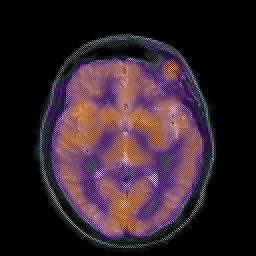

Hypertensive Encephalopathy, overlay -- Slice #12

[Home][Help][Clinical] Slice 12